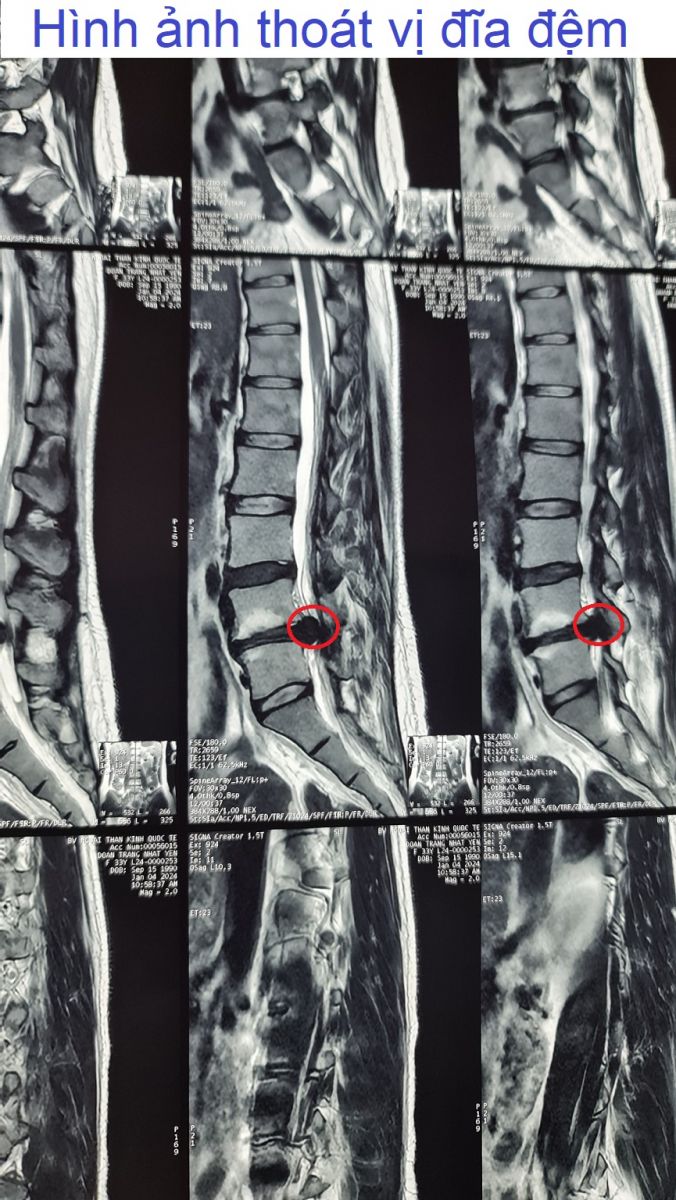

Hình ảnh thoát vị đĩa đệm

Hình ảnh thoát vị đĩa đệm, hình ảnh lồi đĩa đệm, thoái hóa đĩa đệm mất nước.v.v. Đây là những hình ảnh chụp lại trên phim cộng hưởng từ MRI. Kèm theo những kết luận của bác sĩ chuyên khoa cột sống, được Lương y Nguyễn Văn Minh cập nhật liên tục để bạn đọc tham khảo.❮ đọc tiếp ❯

Thoát vị đĩa đệm, rách vòng xơ, chèn rễ L3 trái, chèn rễ L5 phải.Lồi kèm thoát vị đĩa đệm tầng L2-L3, di trú xuống dưới ở ngách bên trái, ép mặt trước bao màng cứng, làm hẹp ngách bên trái, chèn rễ L3 trái. Thoát vị đĩa đệm dạng trung tâm tầng L4-L5, có rách vòng xơ, có mảnh rời di trú xuống dưới ở ngách bên phải, ép mặt trước bao màng cứng, chèn ép rễ L5 phải. Thoái hóa cột sống thắt lưng.❮ đọc tiếp ❯

Thoát vị đĩa đệm dạng trung tâm, có rách vòng xơ.Thoát vị đĩa đệm dạng trung tâm tầng L4-L5, có rách vòng xơ, có mảnh rời di trú xuống dưới ở ngách bên phải, ép mặt trước bao màng cứng, chèn rễ L5 phải. Thoái hóa cột sống thắt lưng.❮ đọc tiếp ❯